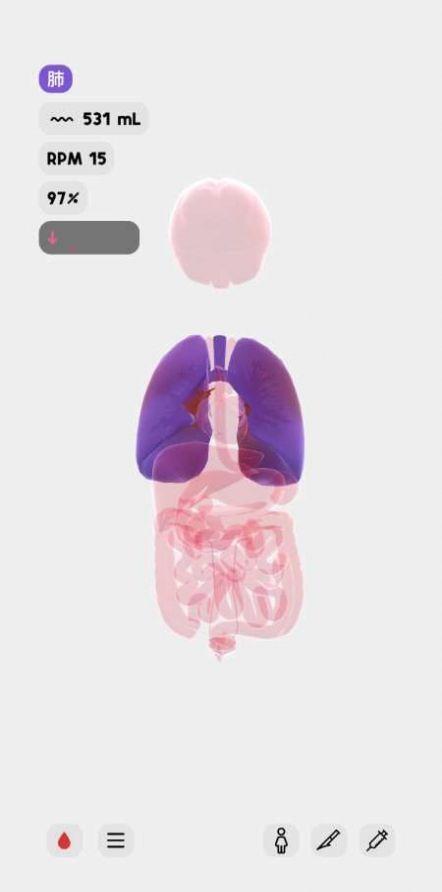

生命人体沙盒模拟器汉化版是一款模拟人体机能的休闲游戏,完全按照真实的医学状况,玩家可以了解不同的器官组成以及工作原理,可以用于研究药物,观察病理,帮助学医的朋友们掌握很多的知识,而且对于普通人也能够更加的了解自己的身体,注意健康不要浪费生命。

非常适合医学生的一款身体模拟器,精致的3D建模,完美还原身体内每个器官的构造,用户可根据学习需要进行移除器官、注射等操作。

1、3d效果呈现,可以清楚的认识每个器官的构造以及各种功能作用;